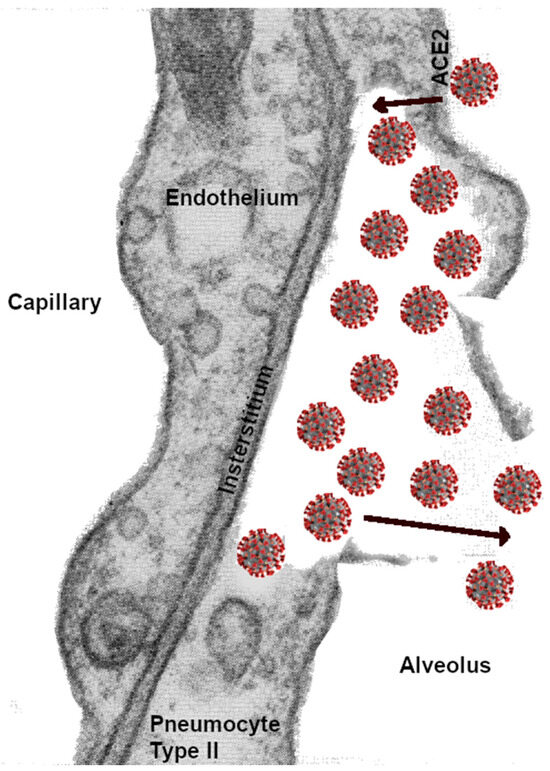

Figure 4.

Diagram depicting a possible scenario of SARS-CoV-2 reproduction within type II pneumocytes, inducing the rupture of the cellular wall and exodus of the coronavirus with replicated RNA, which migrate to infect other pneumocytes. The rupture of the pneumocyte wall would likewise induce alveolar capillary vasodilatation and possible entrance into the circulation and adhesion to endothelial ACE-2 receptors, resulting in coagulopathies. Coughing spreads the virus to other lung segments in both lungs and reduces the alveolar gas-exchange surface area.